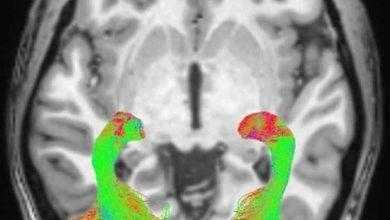

إلا أنه ولأول مرة في دراسة نشرت في مجلة علم الأعصاب، أظهرت الأبحاث التي أجرتها جامعة جونز هوبكنز في بالتيمور أن رفع مستويات فيتامين (د) من شانه أن يخفف من ثورة الجهاز المناعي ويوقف مهاجمته للألياف العصبية.

وينشأ هذا المرض من مهاجمة الجهاز المناعي لغلاف الألياف العصبية (fatty myelin sheath) الذي يعزلها عن بعضها ويساهم في سرعة توصيل الإشارات الكهربائية عبر الأعصاب، ويمكن أن يسبب المرض أعراضا تتراوح بين الوخز الخفيف إلى الشلل الكامل.

ووجد الباحثون أن المرضى الذين يتناولون جرعات عالية من الفيتامين قد انخفضت لديهم خلايا الجهاز المناعي التائية والمرتبطة بنشاط مرض التصلب المتعدد.

وقال الباحثون في مجلة علم الأعصاب: “فوق مستوى معين، فإن كل خمسة نانوغرام لكل مليلتر زيادة في مستويات فيتامين (د) أدت إلى خفض الخلايا التائية بنسبة 1٪. وتقترح الدراسة أن الجرعة القصوى يمكن أن تقلل من الخلايا المناعية الخطيرة بنسبة 8 في المائة.”